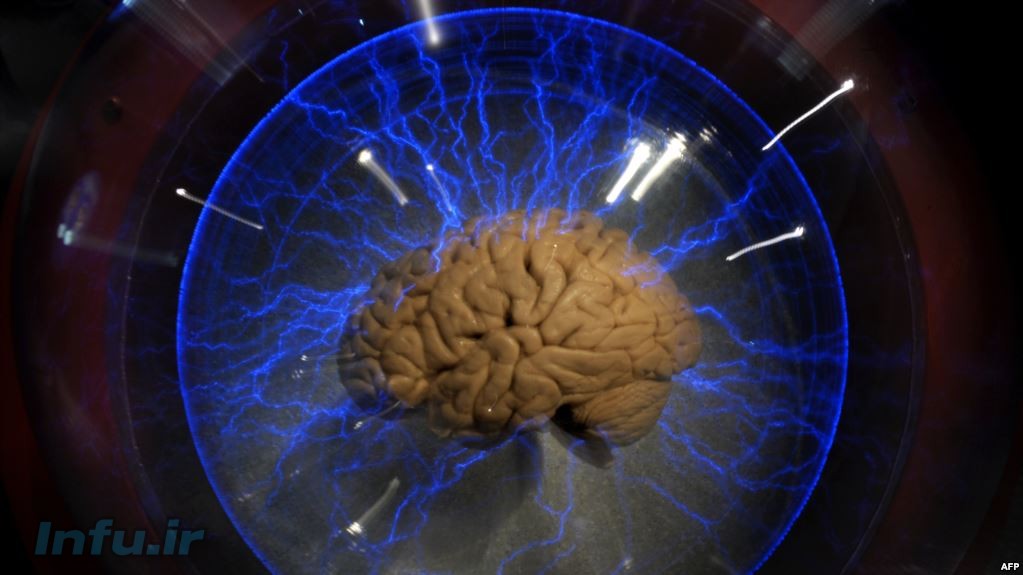

چرا مغز در اوج فعالیت منفجر نمیشود؟

یک پژوهش به مطالعه دلیل عدم انفجار مغز در مواقع اوج فعالیت مانند زمان یادگیری پرداخته است.